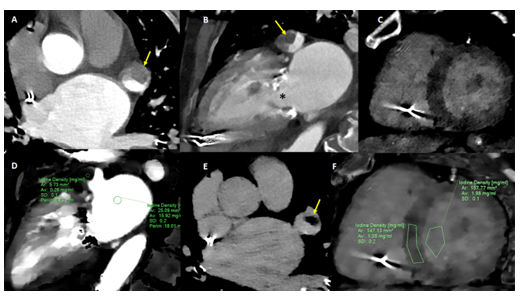

Material y métodos: En el contexto de pandemia de COVID-19 incorporamos la utilización de la TC espectral cardíaca en pacientes con ACVi para descartar en una única sesión, tanto fuentes cardioembólicas (FCE) como la presencia de complicaciones trombóticas o daño miocárdico. A partir de julio de 2020 incorporamos una adquisición tardía a las TC cardíacas en contexto de ACVi. Se presentan cuatro casos representativos sobre su utilidad y hallazgos cardiovasculares.

Resultados: Se presentan cuatro casos registrados en un lapso de 40 días. Dos pacientes con FCE (aorta y orejuela izquierda) y dos con ACVi de origen indeterminado donde se evidenció miocardiopatía (isquémica y no isquémica).

Conclusiones: En el contexto del ACVi, la TC espectral cardíaca, que incluía adquisición tardía, permitiría, eventualmente, descartar la presencia de FCE e identificar la etiología subyacente.